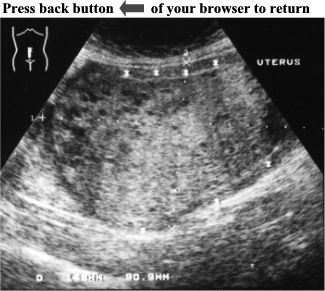

CASE

2:

Pelvic

ultrasound

of

this

female

patient

revealed

an

enlarged

uterus

(15.8cm

X

9.1cm).

There

was

a

large,

non-homogeneous,

solid

mass

filling

whole

uterus.

Several,

small

anechoic

structures

were

scattered

all

over

the

where

it

surrounded

by

normal

myometrium

(see

asterisks).

ANSWER:

Complete

Hydatidiform

Mole